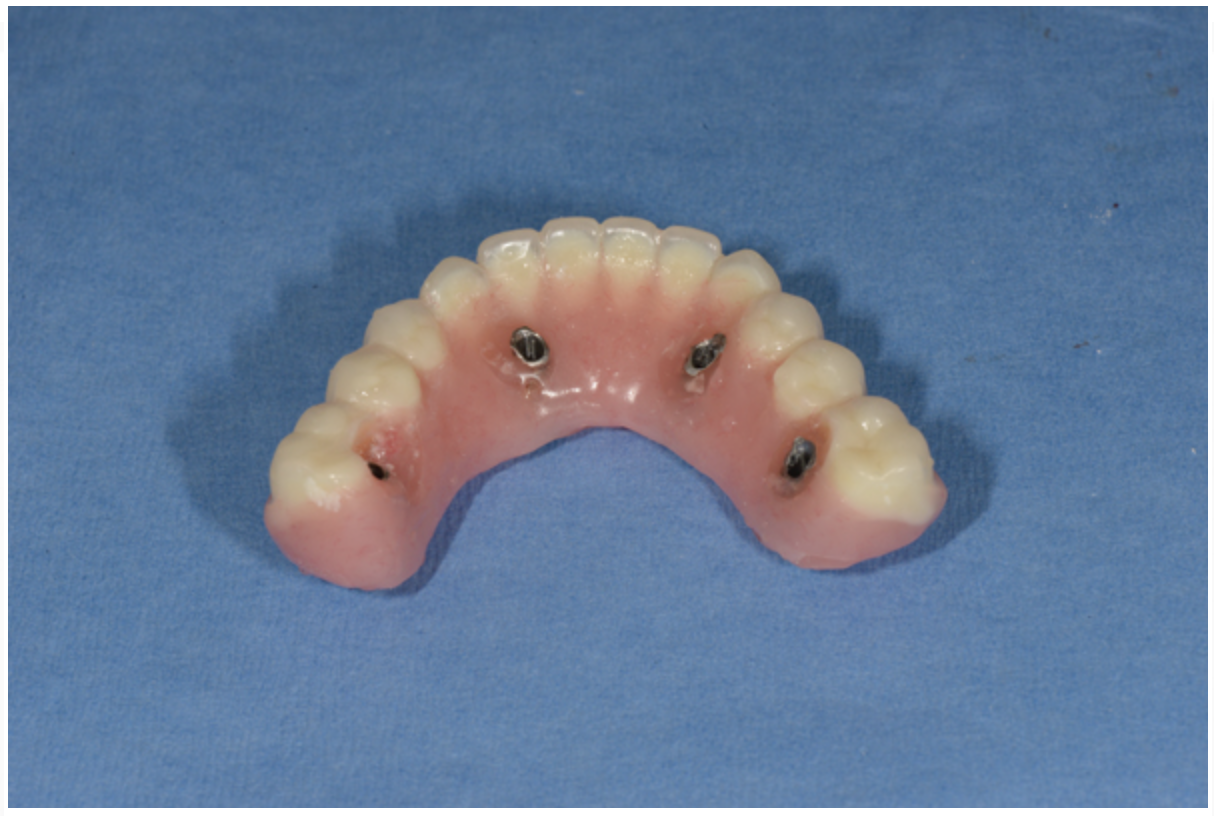

Fig 16. Indirect denture conversion—The indexed provisional prosthesis is modified for passive attachment of the posterior titanium cylinders to the prosthesis using heat-cured acrylic under pressure. This process is repeated for the anterior indexed implants, leading to a higher quality provisional with increased strength.

Figure 16

The dental technician fabricates a master cast with a soft-tissue model while the indexing and VDO procedures are performed. A silicone material is added around the implant analogues in the surgical impression before model pouring with zero expansion stone (Figure 14 and Figure 15). The soft-tissue model is removed to verify a precise fit of the temporary titanium cylinders indexed in the mouth to the master cast. The indexed provisional prosthesis is modified to allow passive attachment of the posterior temporary cylinders to the prosthesis using heat-cured acrylic processed under pressure. The technician then removes the cold-cure acrylic that was used to index the two anterior temporary components and re-secures them with fresh heat-cured acrylic under pressure (Figure 16). The intaglio surface of the provisional prosthesis is finished with cold-cure acrylic on the master cast and polished to ensure a convex surface with sufficient space to allow for tissue swelling and access for hygiene.